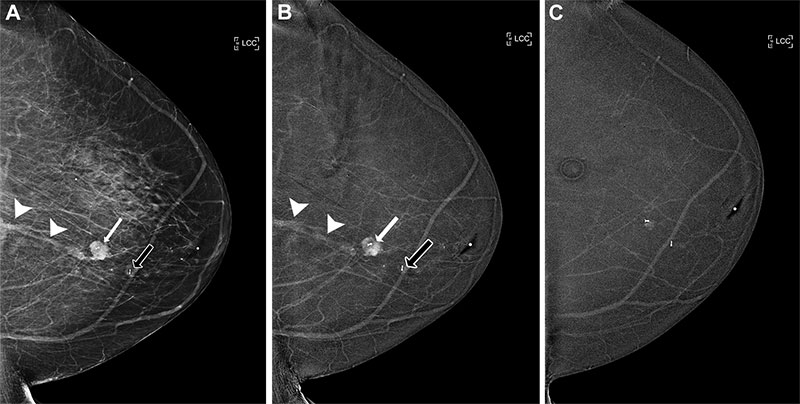

Eye Gaze AI System Enhances Diagnostic Performance

Perceptual errors are a key challenge to diagnostic accuracy, accounting for between 60% and 80% of diagnostic mistakes. They occur when radiologists fail to detect or incorrectly interpret abnormalities because of visual oversight during initial image interpretation.

New studies on eye gaze data have shown a direct correlation between eye movements and diagnostic decision-making. The nonintrusive nature of eye gaze recording means that it can be seamlessly integrated into clinical workflows.

A team led by Akash Awasthi, a PhD candidate from the Department of Electrical and Computer Engineering at the University of Houston, developed a personalized AI system that integrates eye gaze data and radiology reports. Their research, published in Radiology: Artificial Intelligence, aims to improve the diagnostic accuracy of chest radiograph interpretation through the identification and correction of perceptual errors.

In two simulated datasets, the AI system, Collaborative Radiology Expert (CoRax), corrected 21.3% and 34.6% of errors on chest radiographs, respectively. The system also demonstrated its potential use in diagnostic decision-making across various abnormalities of chest radiographs.

“CoRaX differs fundamentally by functioning as a collaborative assistant: It supports radiologists by identifying potential perceptual oversights and offering interpretable, gaze-informed feedback,” the authors note.

Read the full article “Collaborative Integration of AI and Human Expertise to Improve Detection of Chest Radiograph Abnormalities.”